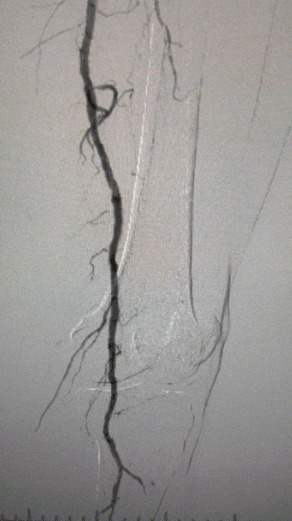

・術前イメージング: 両側下肢動脈における重度のびまん性石灰化狭窄症

複雑な血管状態を考慮して、ThorCrack末梢IVLバルーン拡張カテーテルシステムを選択しました。 患者の耐性が限られているため、両方の下肢に段階的な介入手順が実行されました。

外科的成果

処置後、動脈狭窄は大幅に改善し、血流が増加し、皮膚の温度が上昇しました。 術後の合併症は発生しませんでした。 患者と外科チームの両方が結果に非常に満足していました。